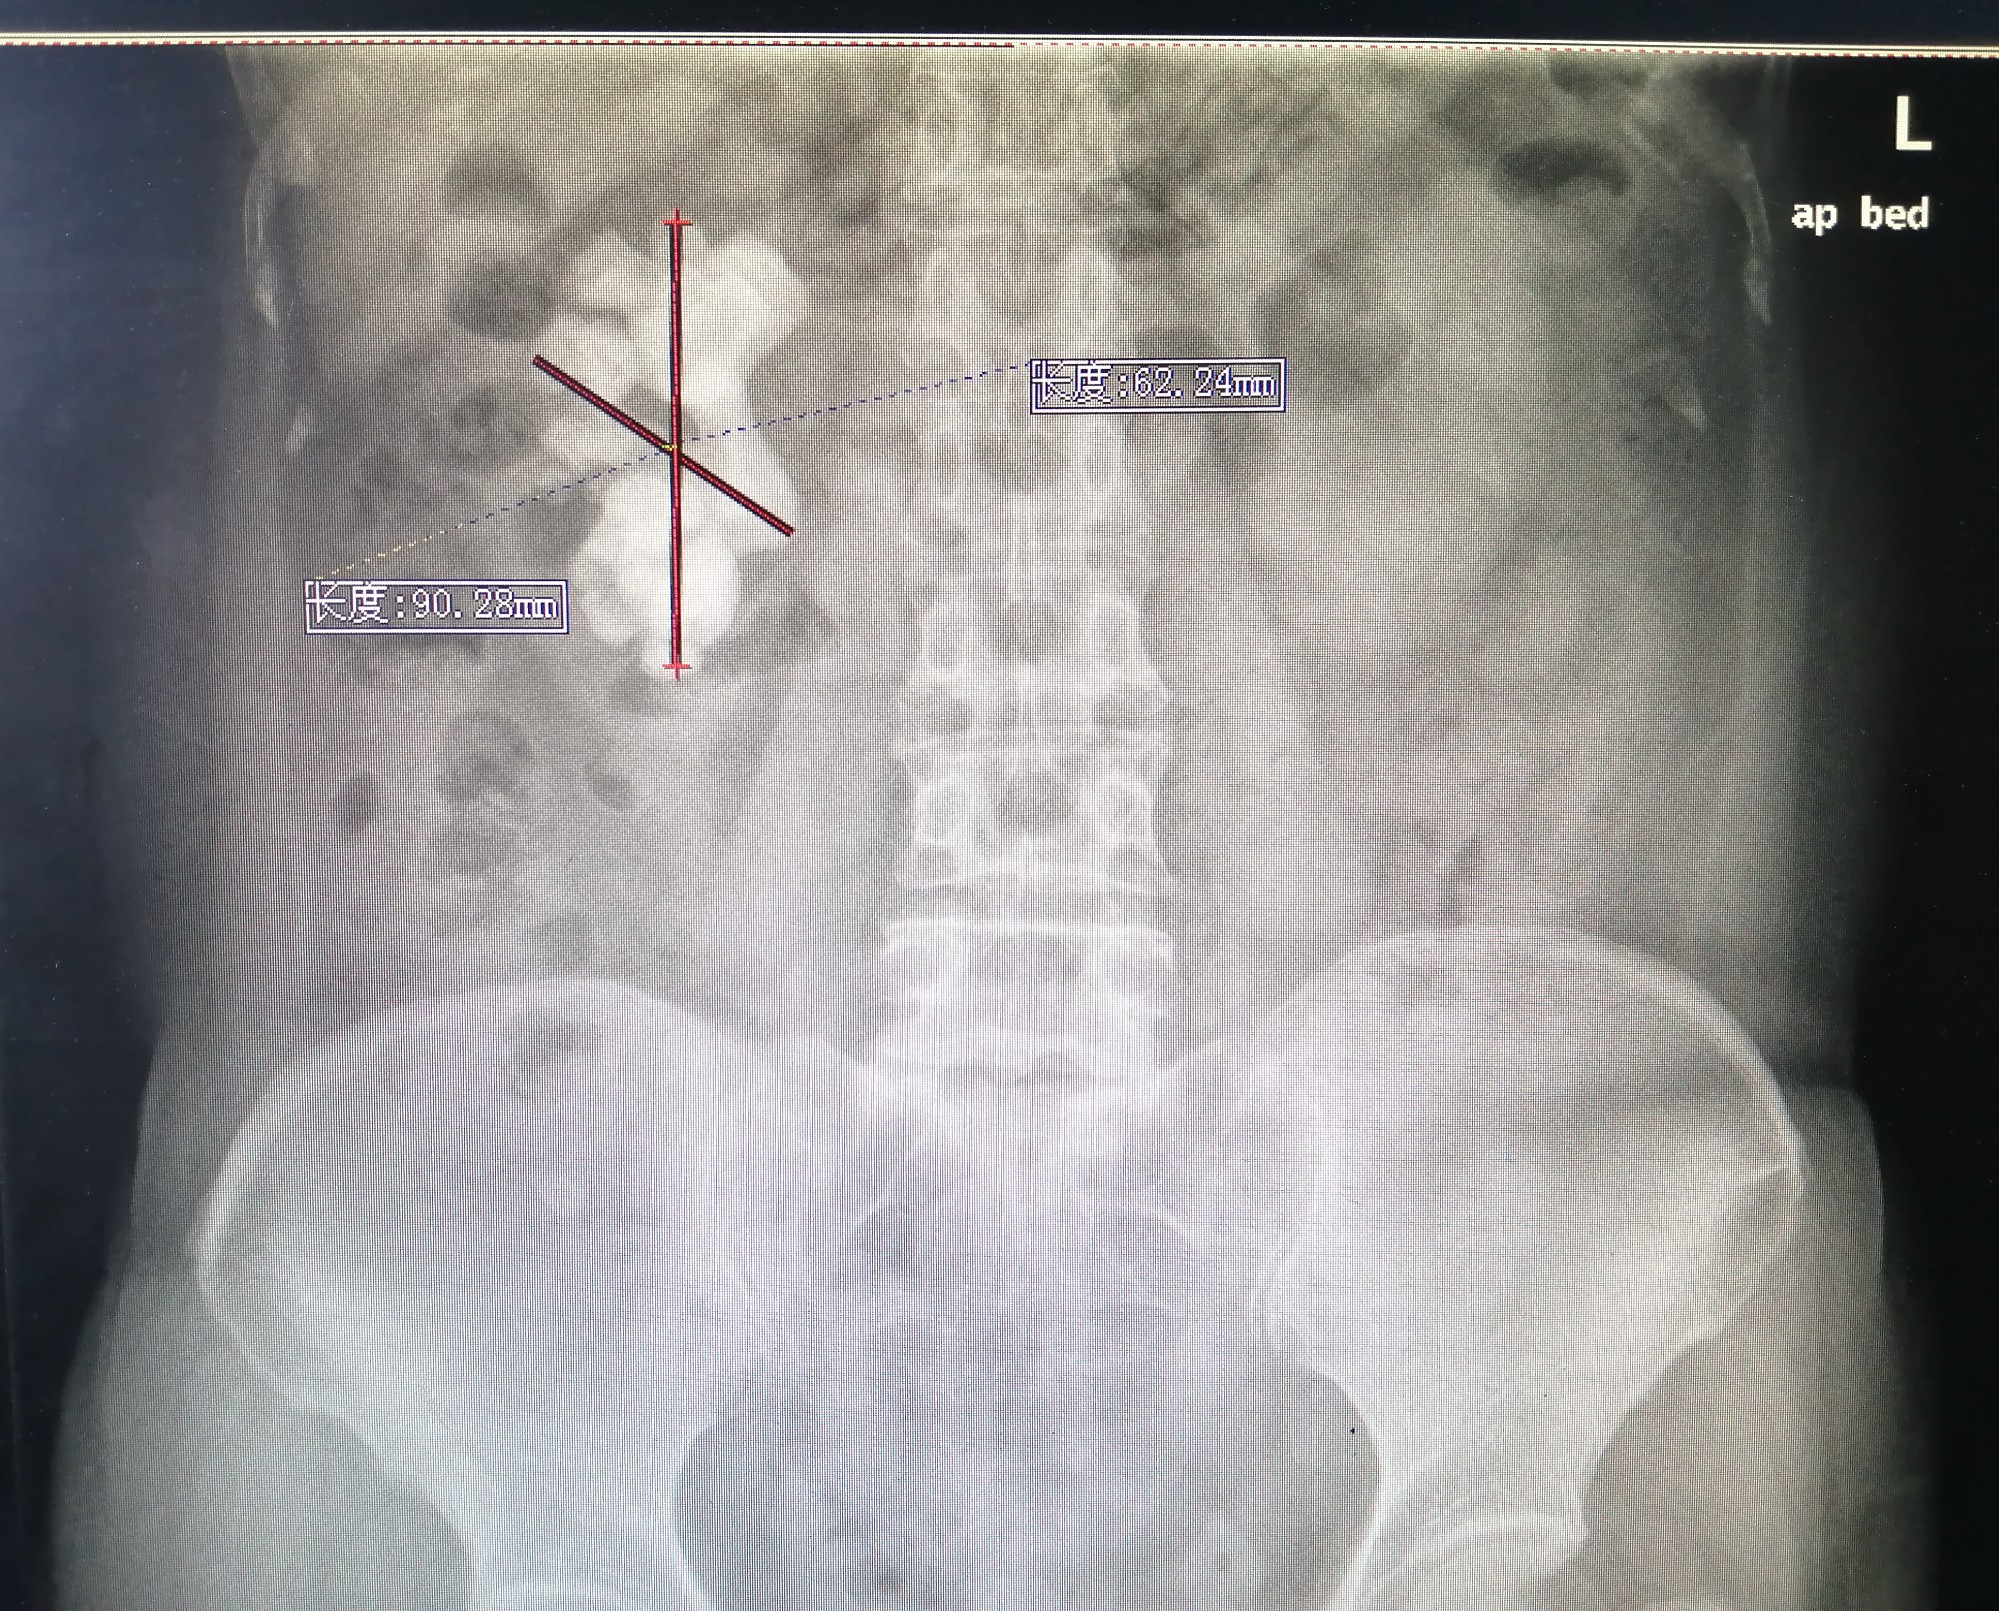

接受“碎石航母”治疗的首例患者是55岁的王女士。长期以来,王女士饱受腹部疼痛的困扰,来医院检查后,影像学资料显示王女士肾结石最长直径约9cm。在与患者及家属沟通后,王女士主动选择使用第五代EMS治疗,于是在开机当天,泌尿外科团队成功为王女士完成结石手术。3月26日,王女士复查影像学结果显示,结石已全部清除干净,且术后效果良好。